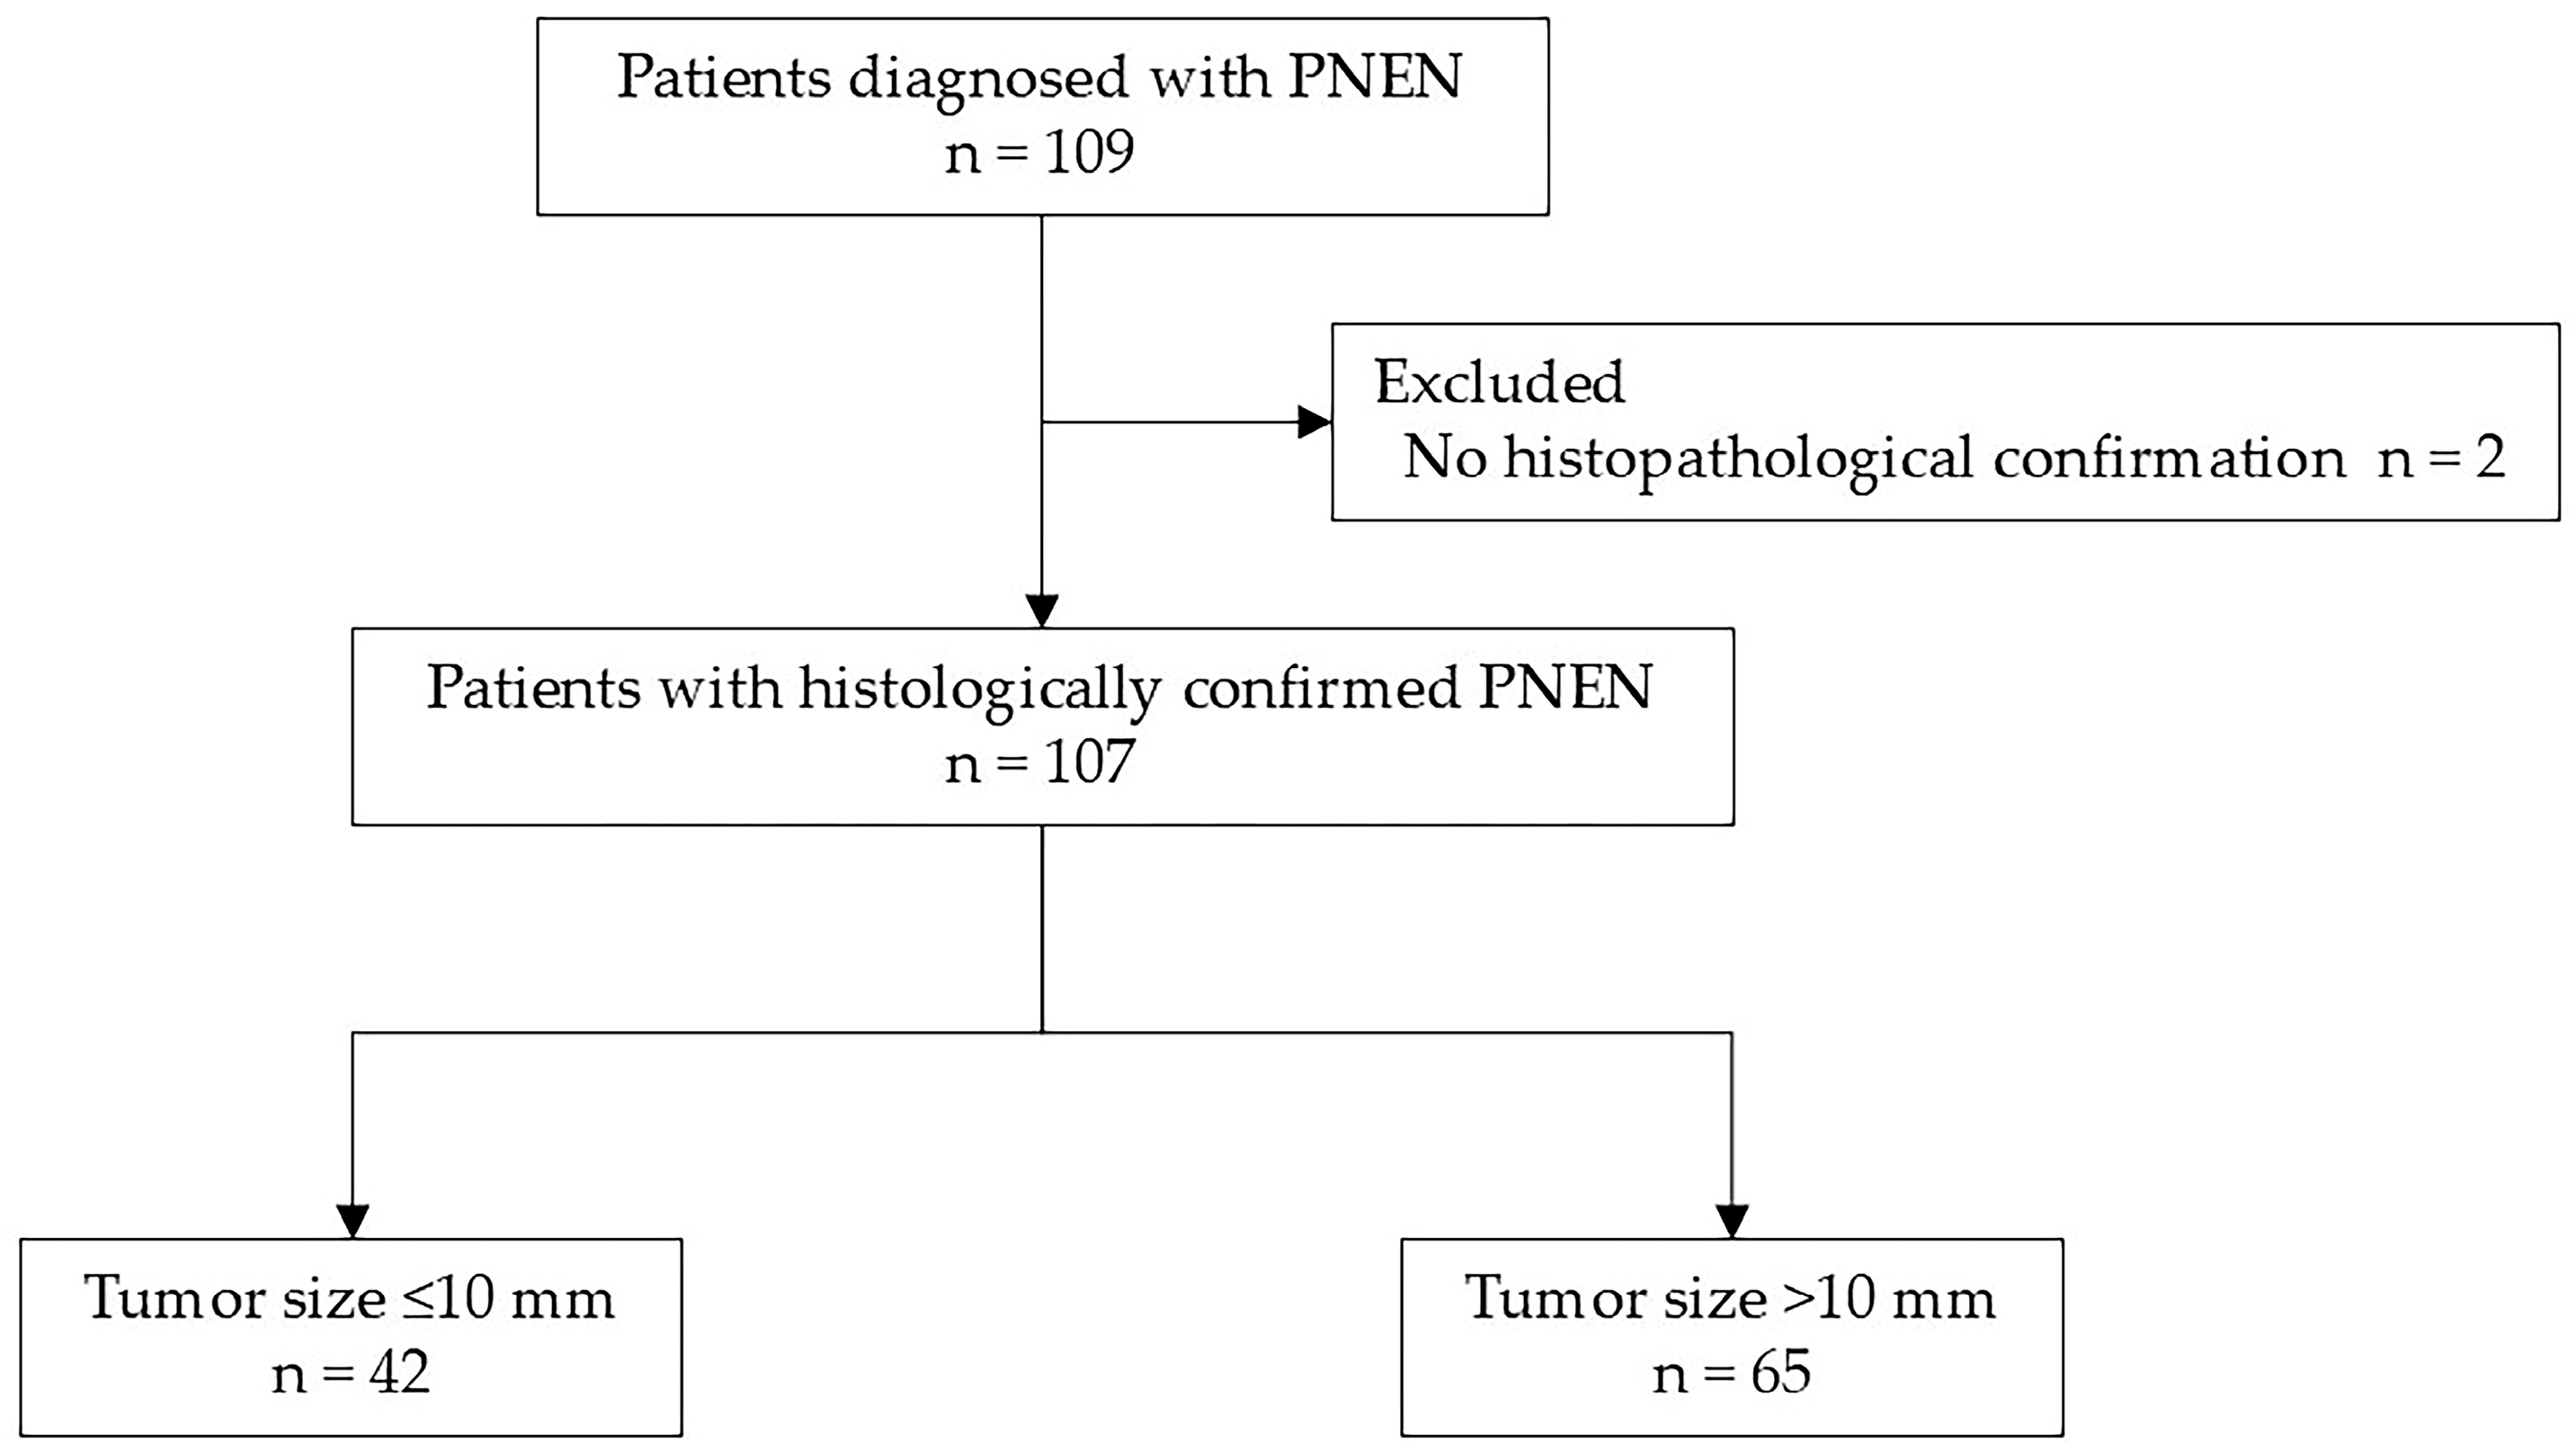

2. Materials and Methods

2.1. Participants